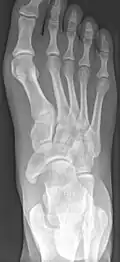

-

From left to right: Type 1, 2 and 3 -